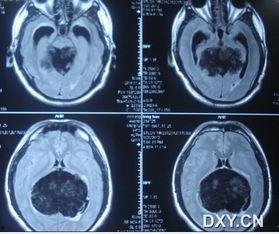

肿瘤照片,揭示癌症的视觉秘密